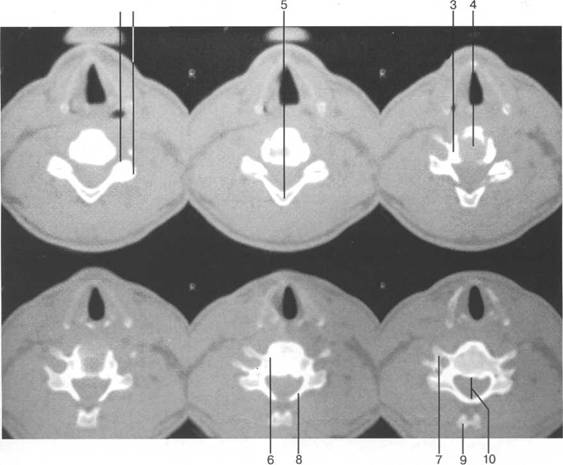

fossa rhomboidea; pedunculus cerebellaris sup.; pedunculus cerebellaris medius; n. trigeminus; n. facialis; n. vestibulocochlearis; margo sup. partis petrosae; pedunculus cerebellaris inf.; tuberculi nuclei cuneati; tuberculi nuclei gracilis; sinus sigmoideus; n. glossopharingeus; n. vagus; n. accessories; n. hupoglossus; processus mastoideus; N.C. I; intumescentia cervicalis; radix dors.; ramus ventr. n. spinalis IV; ramus dors. n. spinalis IV; fasciculus gracilis; fasciculus cuneatus; ganglion spinale (Th. I).